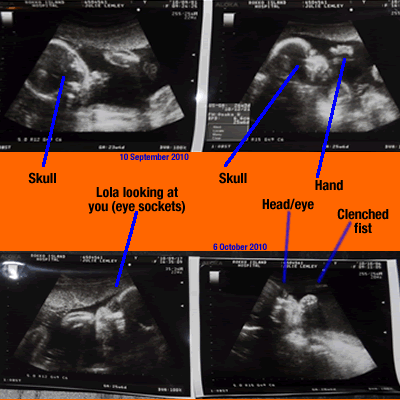

And this is what the little lady looks like:

I get ultrasound pictures every time I have a doctor's appointment, which is a perk of having a baby outside the US. Unfortunately, my doctor likes to get "head on" shots of the baby. All the photos are creepy alien -like vacant-eyed skull shots. Not those cute, profile, baby shots you normally see. So, I'll spare you those shots, or maybe I'll make a photo montage for Halloween.